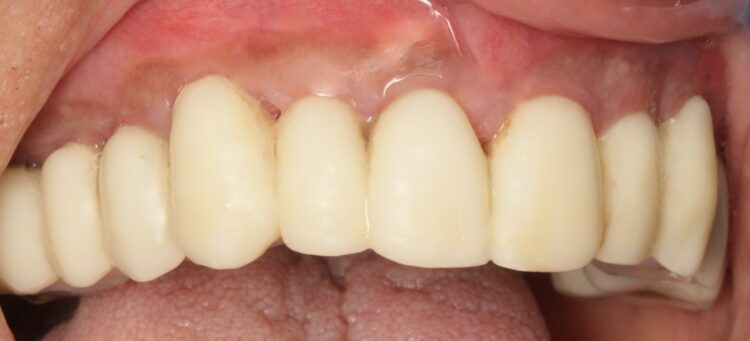

Based on the digital design and copying the approved provisional prosthesis, a zirconia overlay was milled. The overlaying zirconia superstructure was digitally designed to fit the metal substructure, accomplish a flawless finish line, avoid any undercuts and verify the path of insertion, thus facilitating the bonding procedures. The zirconia superstructure was bonded with the titanium substructure using a self-curing luting composite. The final polished screw-retained prosthesis was delivered and torqued to 30Ncm and the radiographic assessment was executed.

After the follow up appointments at one and four weeks, the patient was scheduled for periodic maintenance every three months. The retrievability of the final screw-retained zirconia-titanium supported prosthesis allowed management of the interface over time. At the one-year review, further growth and maturation of the soft tissue as well as the health of the keratinised peri-implant tissues were evident, without signs of bleeding on probing.

The patient was thrilled with the final outcomes achieved in this case, as was I. The failing dentition was replaced by a fixed, long-term – with patient oral hygiene compliance – and cleansable solution, which will restore the patient’s quality of life.

Particularly in FP1 cases where a correct emergence profile has to be formed through the implant-supported immediate temporary prosthesis, a digital treatment plan and guided surgery offer a comprehensive workflow to achieve predictable high-end prosthetic results that mimic the natural dentition.

The translucent zirconia supported by titanium framework fulfils the aesthetic and mechanical requirements of an FP1 full arch prosthesis, while minimising the risk of fracture by providing a rigid yet passive joint to support the implants.[vi] The zirconia and titanium transmucosal surface characteristics (otherwise known as biocompatibility) create a highly polished interface for high cell adhesion and optimised gingival architecture.